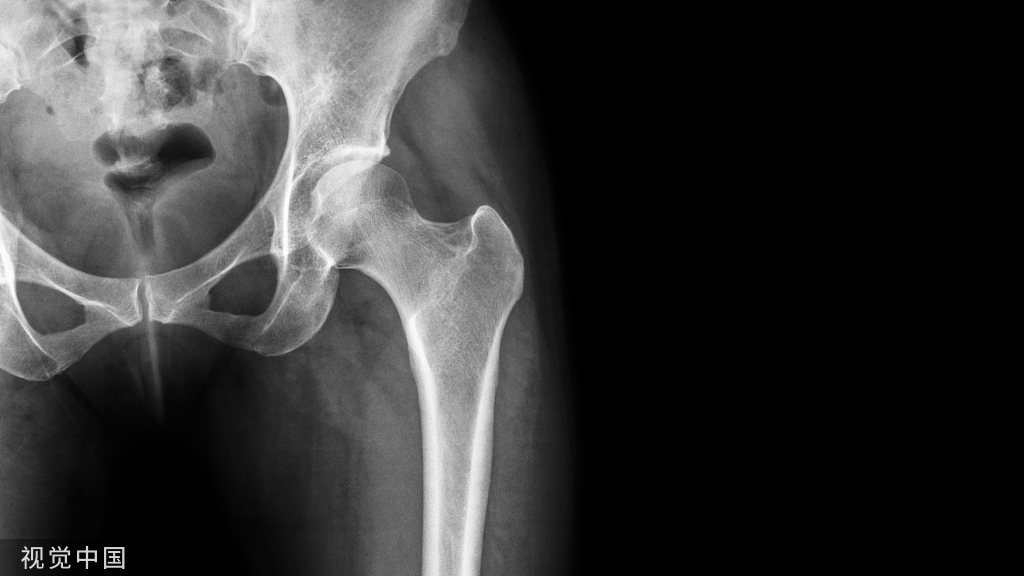

内固定术是用金属螺钉、接骨板、髓内针、钢丝、钛缆或骨板等物直接在骨内或骨外将骨折、关节或脊柱连接固定起来的手术。

内固定物的作用是为了维持稳定,如骨折对位对线后,使用内固定物维持对位对线并固定牢固;又如关节融合手术,为了维持准备融合关节的稳定以便关节融合,需要相应固定材料进行固定;还比如脊柱退变手术,为了维持脊柱的稳定,避免出现或者为了纠正脊柱不稳,也需要内固定来维系。因此,在骨科很多手术中,进行内固定术是必不可少的。

一旦骨折愈合、脊柱融合、关节融合等,内固定物就完成了使命,也就是说内固定物“没用”了,再加上内固定物材料大多系金属材质(目前有些内固定物是可吸收材料,不在我们这次的讨论范围),对人体来说总归是异物。因此,大多数人都认为这时内固定物就应该取出来了。

对于广大患者来说,内固定物取出以后才能算是骨折治疗的真正结束。然而,我们如果想要取出内固定物,必须了解取出内固定物的费用、效用和危险。取内固定物前必须进行影像学检查,确定骨折已经完全愈合,结合最新的影像学资料和病历了解内固定物的目前情况和位置。